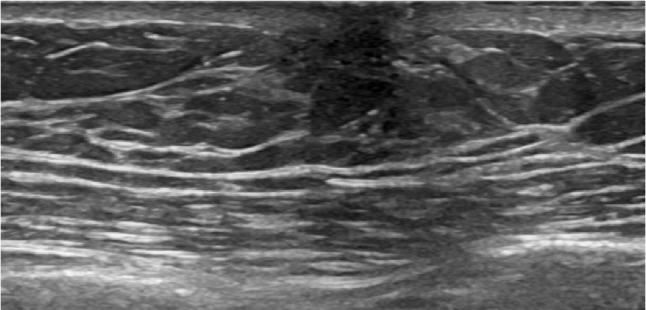

Case presentation: This report presents a unique case of PASH in a senior adult male, aged over 65 years, who presented with an enlarging palpable areolar mass. Notably, the patient had no family history or past medical history of breast cancer. Imaging studies, including mammography and ultrasound, revealed mild gynecomastia and BIRADS-4 classification, prompting further investigation. A core needle biopsy confirmed the diagnosis of PASH, showing no evidence of carcinoma or malignancy. Given the mass's progressive enlargement, surgical excision was recommended and successfully performed.